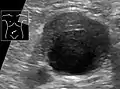

Ultrasonography of an aneurysm with a mural thrombus